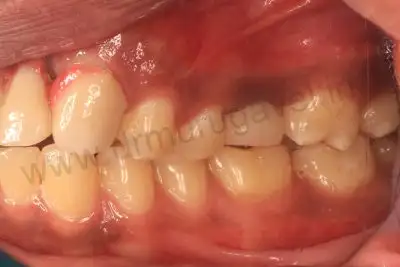

Before treatment image

Front teeth replacement with Implants

- It should be noted that his provisional bridge had hygienic gaps in the gum region , this denotes perfect gum healing and the implants condition was confirmed after taking radiographs ( OPG & CBCT ).